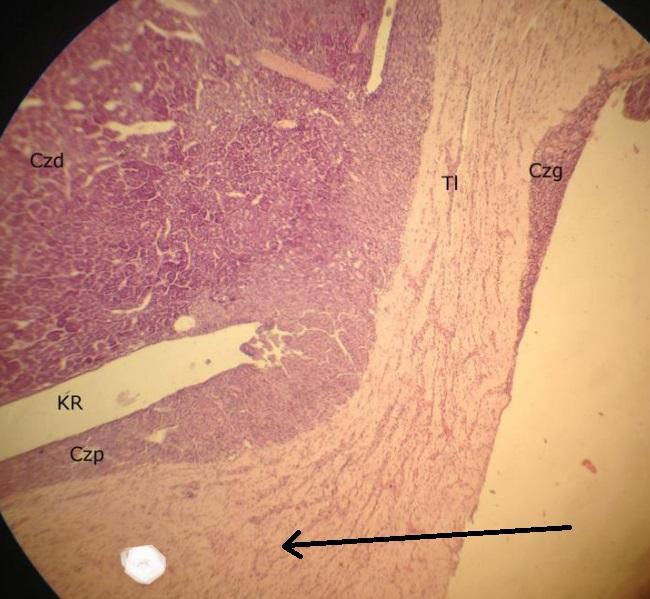

tkanka łączna dzieląca przytarczycę na pseudopłaciki